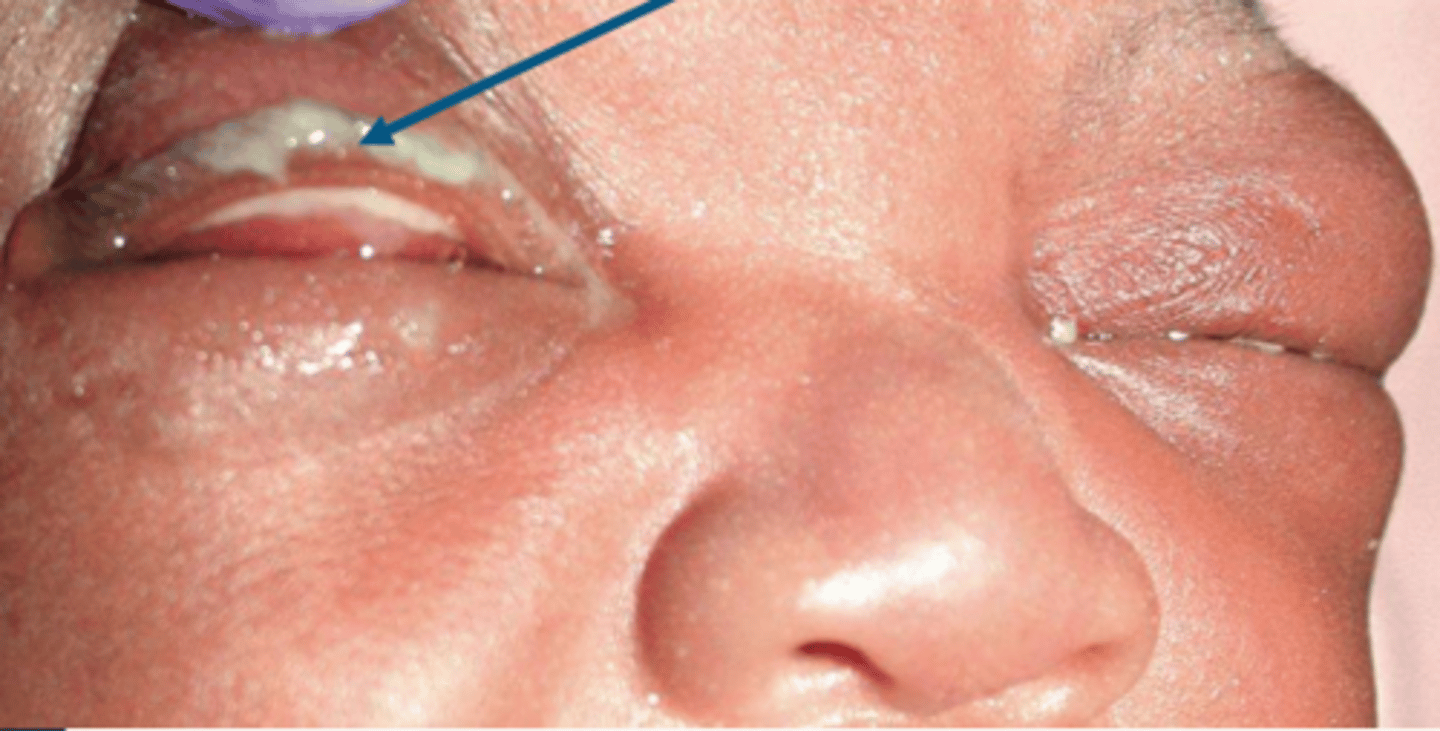

_____ is the acute or hyper acute inflammation of the conjunctiva in newborns within the first 28 days of light because of the chemical insult or microbial infections

neonatal conjunctivitis or neonatal ophthalmia

neonatal ophthalmia/ neonatal conjuctivitis

neonatal ophthalmia/ neonatal conjunctivitis

someone with neonatal conjunctivitis would experience (5)

pain, discharge, tenderness, redness, and eyelid crusting